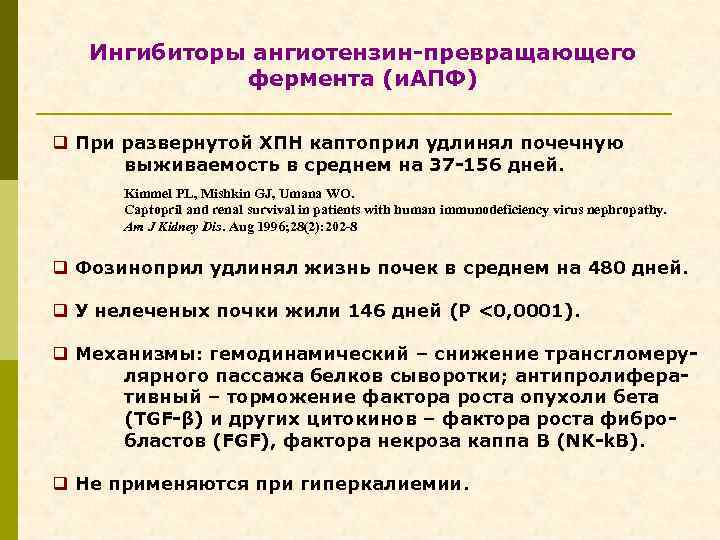

Ингибиторы ангиотензин-превращающего фермента (и. АПФ) q При развернутой ХПН каптоприл удлинял почечную выживаемость в среднем на 37 -156 дней. Kimmel PL, Mishkin GJ, Umana WO. Captopril and renal survival in patients with human immunodeficiency virus nephropathy. Am J Kidney Dis. Aug 1996; 28(2): 202 -8 q Фозиноприл удлинял жизнь почек в среднем на 480 дней. q У нелеченых почки жили 146 дней (P <0, 0001). q Механизмы: гемодинамический – снижение трансгломерулярного пассажа белков сыворотки; антипролиферативный – торможение фактора роста опухоли бета (TGF-β) и других цитокинов – фактора роста фибробластов (FGF), фактора некроза каппа В (NK-k. B). q Не применяются при гиперкалиемии.